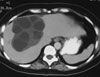

An abdominal CT scan is ordered.

The CT scan shows a large cystic lesion with multiple internal septations. This finding in an asymptomatic patient with hepatomegaly who was raised on a farm in Greece strongly suggests cystic echinococcosis, D.